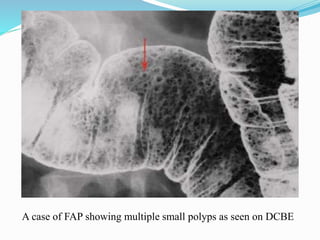

This document discusses colorectal polyps. It defines polyps and describes their types, including neoplastic and non-neoplastic polyps. It discusses adenomatous polyps in depth, noting their malignant potential increases with size over 1cm and villous architecture. Radiological diagnostic methods for polyps including single and double contrast barium enema and CT colonography are explained. The document provides an overview of polyp pathogenesis and genetic syndromes like FAP that increase cancer risk.